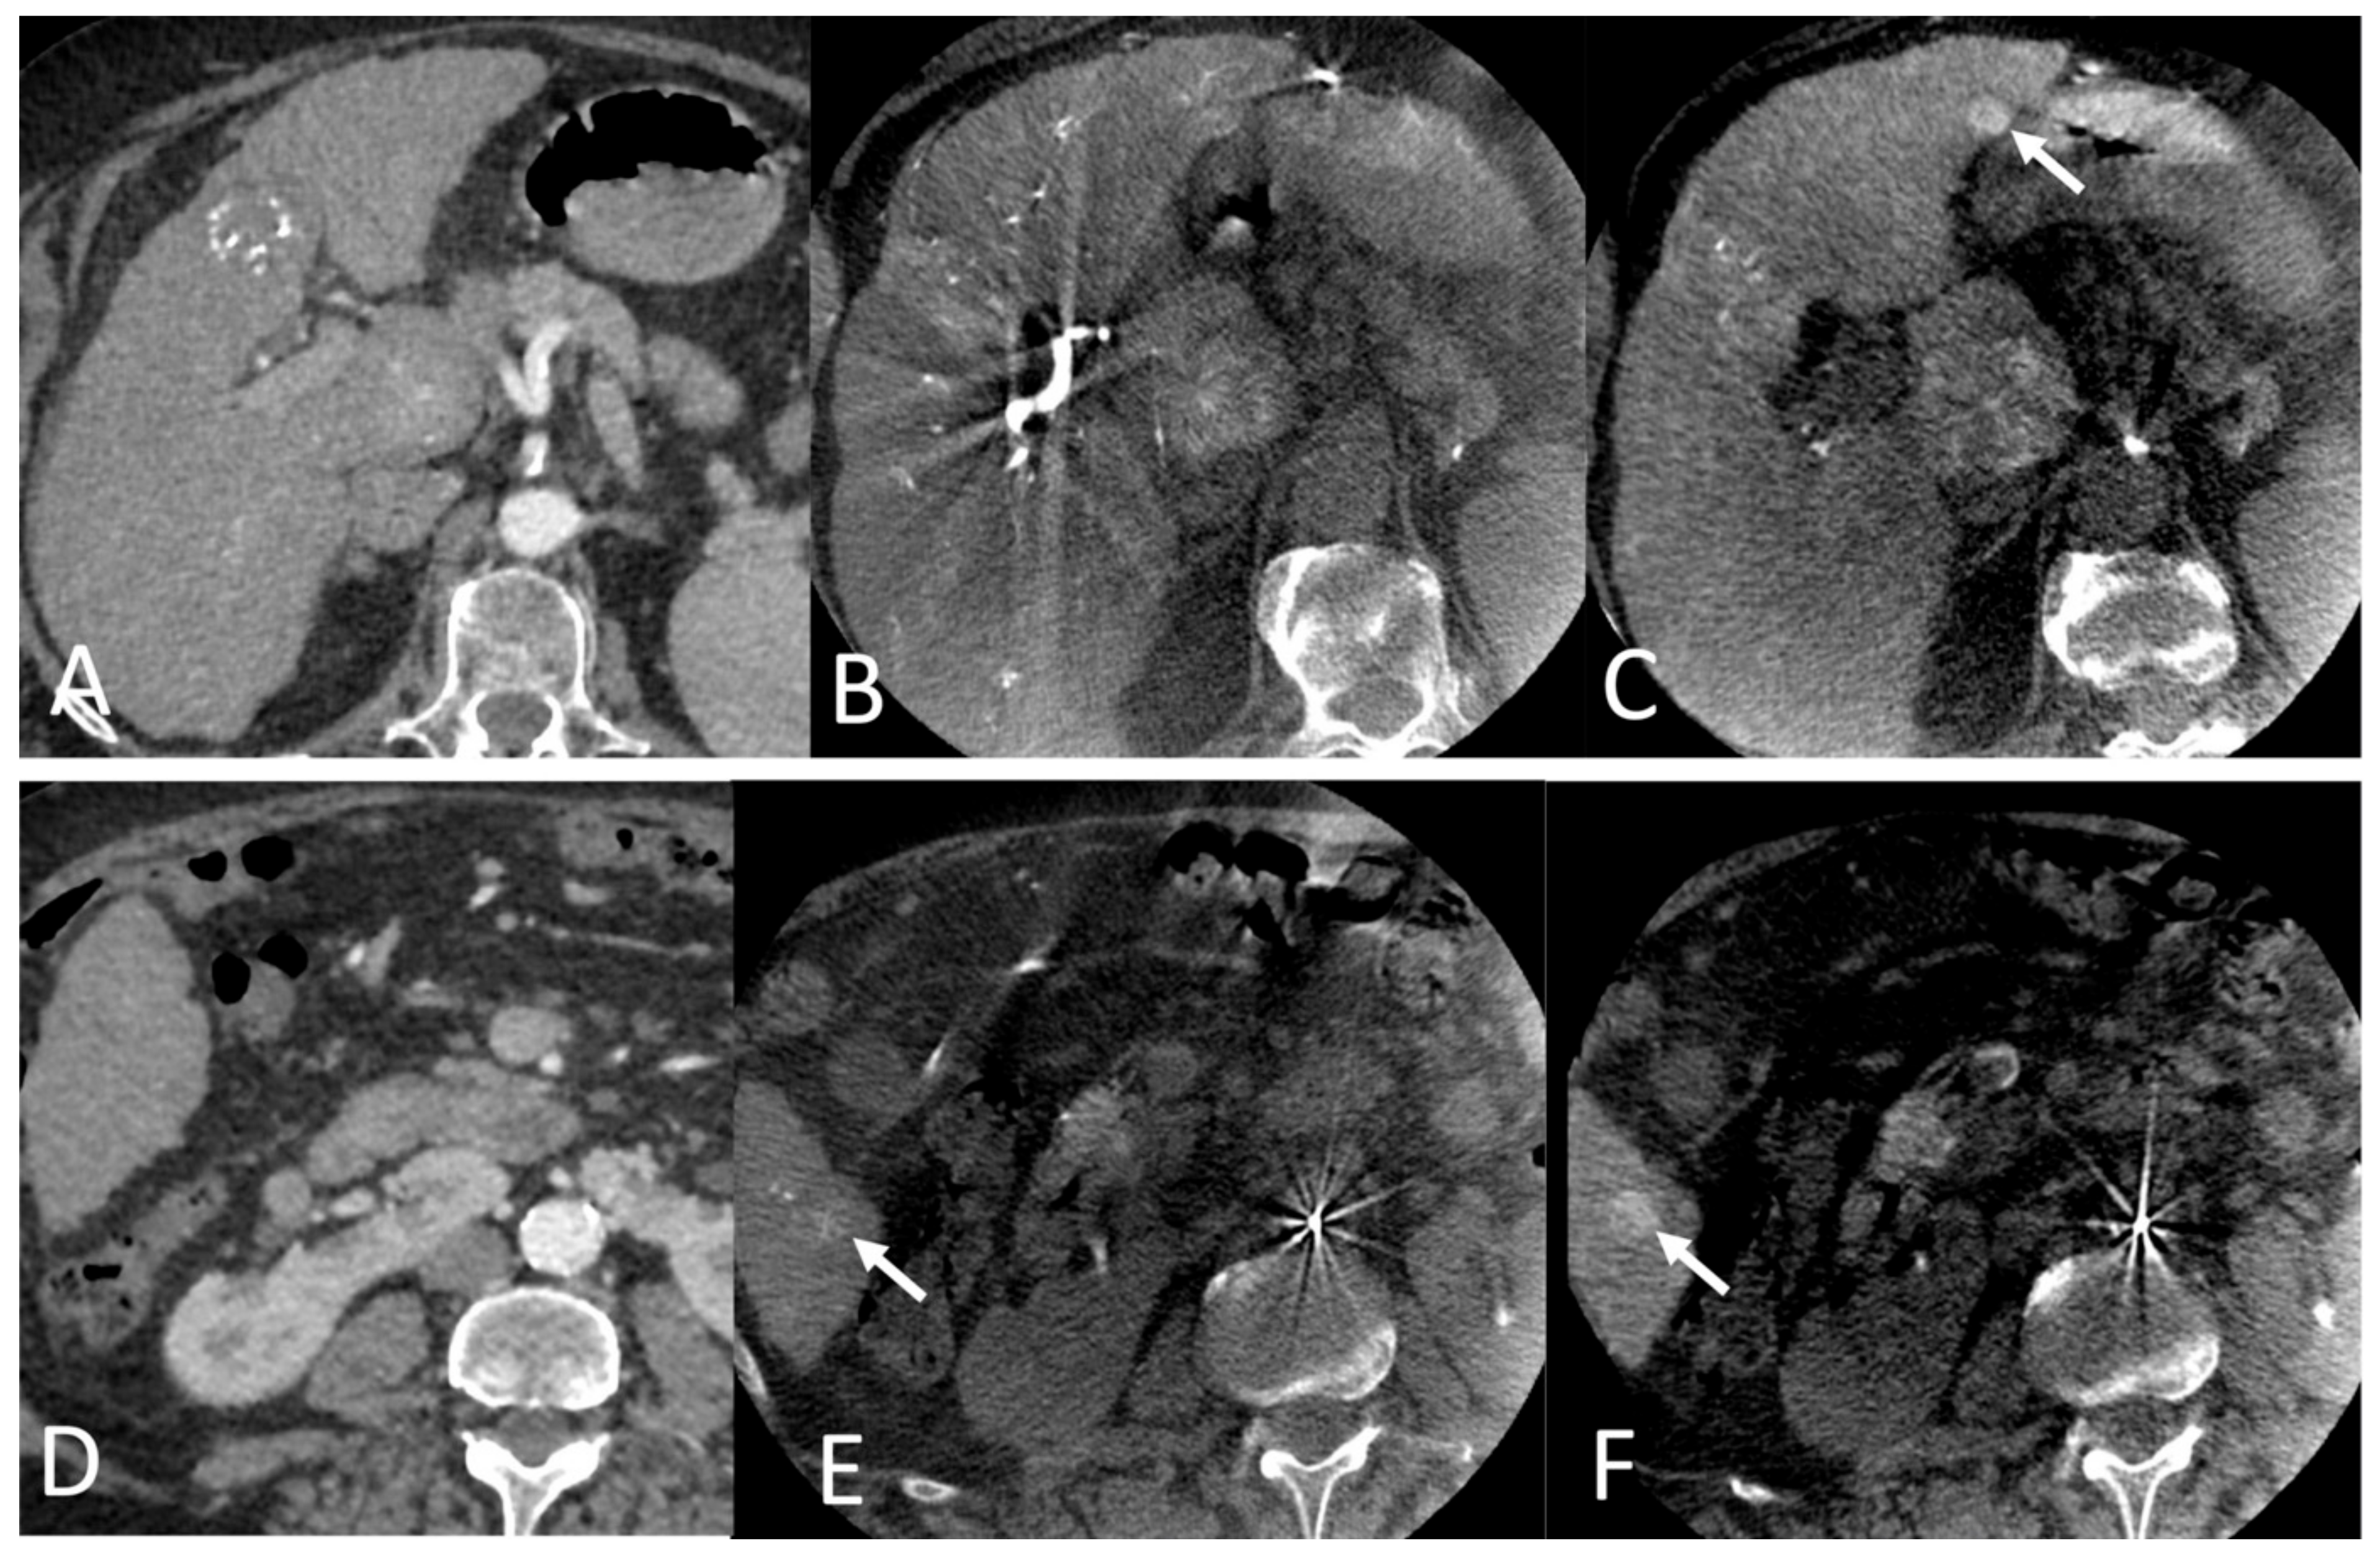

2.3. Per-Interventional Imaging

2.4. Imaging Analysis

3.2. Imaging Data Analysis